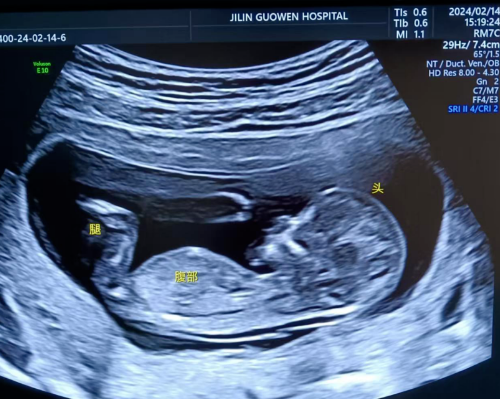

超聲檢查,孕婦無需空腹。檢查時,超聲醫(yī)生會使用超聲儀器對胎兒頸部進行仔細觀察和測量。通過超聲探頭可以清晰地看到胎兒在子宮內(nèi)的情況,重點測量胎兒頸項部皮下無回聲透明層最厚的部位,測量值即為 NT 值。正常胎兒 NT 值一般不超過 2.5mm。